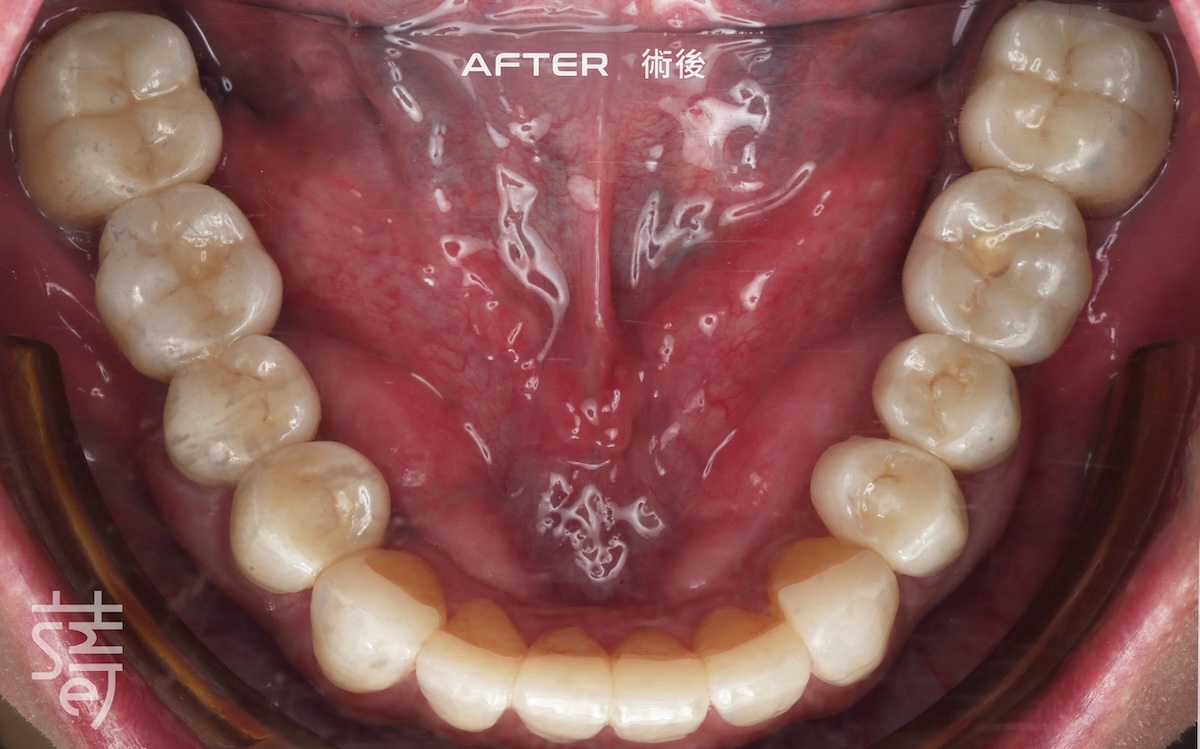

經過一段完整而細緻的治療,李先生終於重新露出久違的笑容,自然、上鏡,也能自在享受每一口美食。

After a thorough and meticulous treatment, Mr. Li finally revealed a long-lost smile—natural, camera-ready, and able to enjoy every bite with ease.

從矯正、植牙、臨時假牙的調整,到最終假牙的完成,每一步都凝聚著薛醫師的專注與團隊的細心。透過 Modjaw 的動態咬合紀錄與國際專家的臨床經驗,蒔美讓李先生的笑容不只漂亮,更兼具穩定與健康。

From alignment, implants, and temporary prosthetic adjustments to the final restoration, every step reflected Dr. Xue’s focus and the team’s care. With Modjaw’s dynamic bite records and international expertise, Smile ensured Mr. Li’s smile was not only beautiful but stable and healthy.

這份「自然」不是偶然,而是從每一個細節累積而來的用心。蒔美相信,能長久陪伴日常的笑容,才是真正屬於你的美好與自在。

This “natural” result wasn’t by chance—it was built from meticulous attention to every detail. Smile believes that a smile that lasts through everyday life is the one that truly belongs to you.